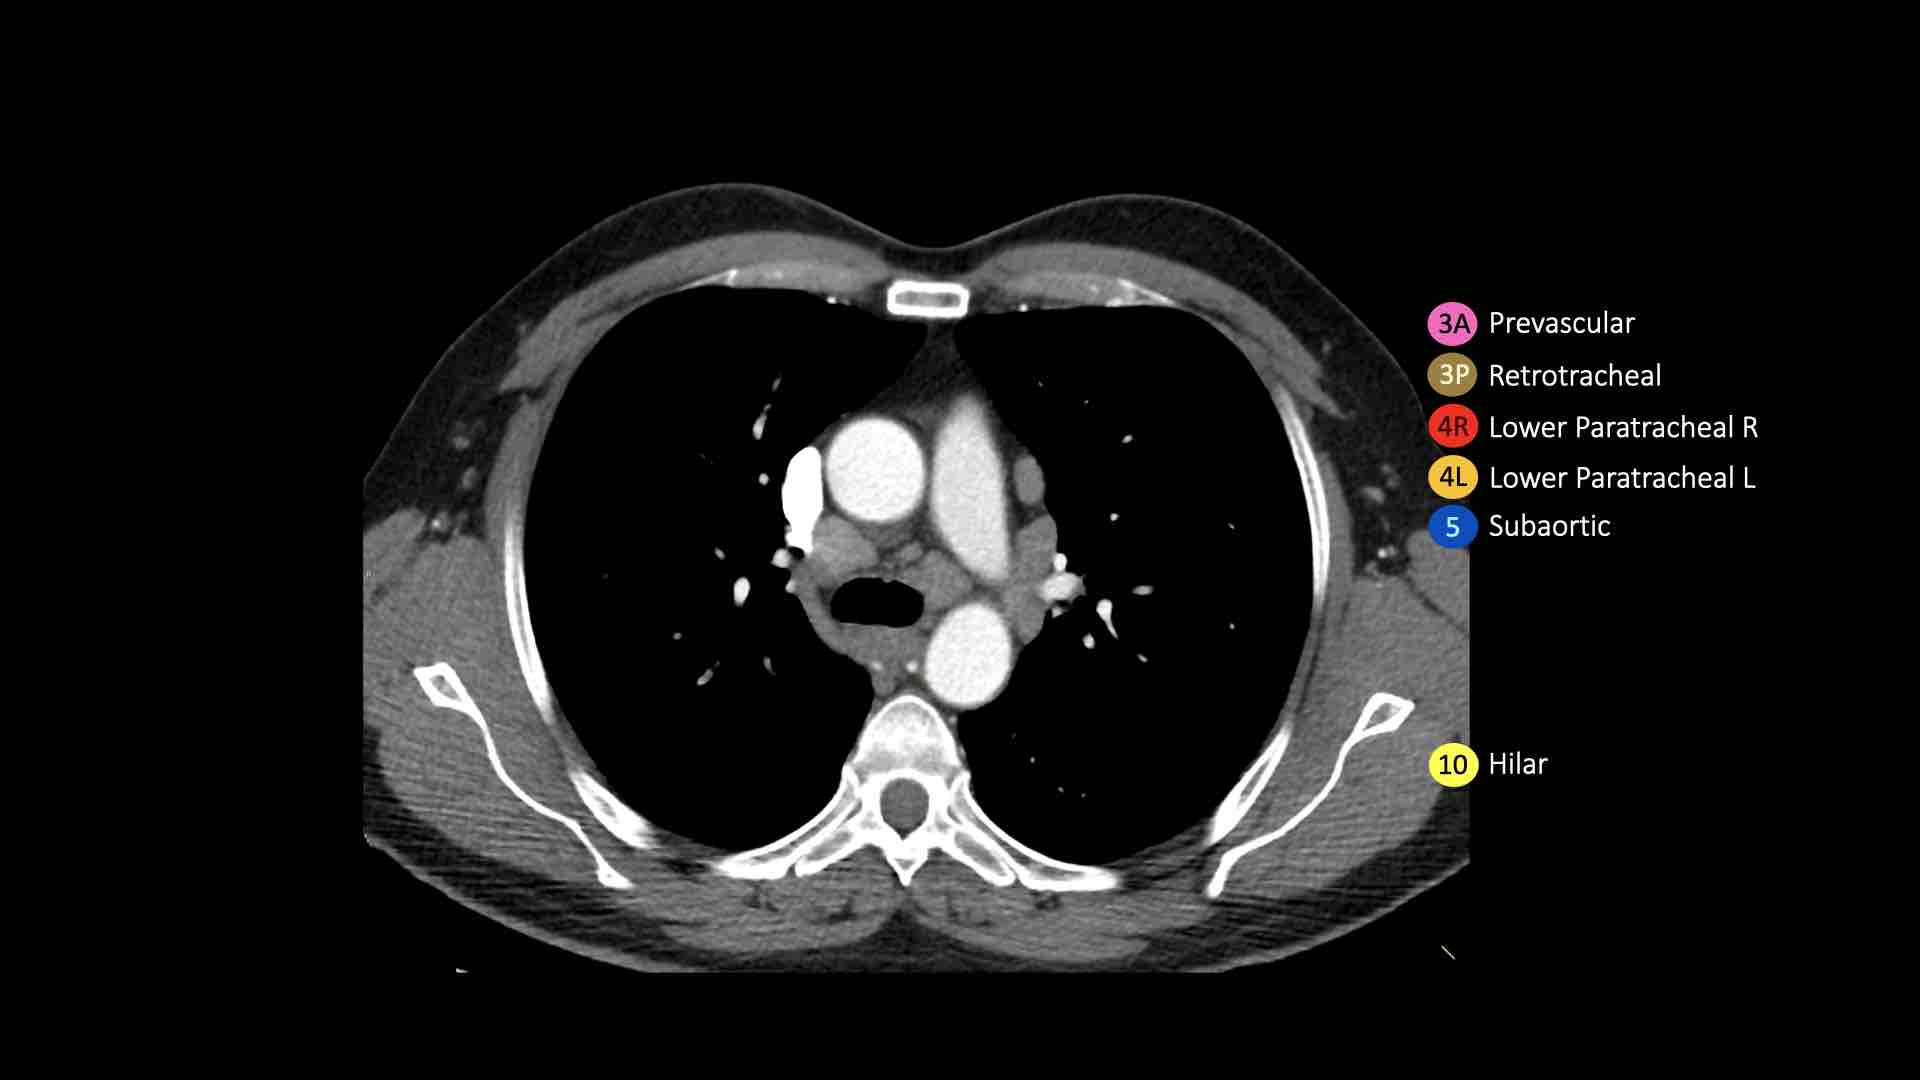

10. Hạch rốn phổi

Hạch rốn phổi là các hạch thùy gần, nằm ở phía xa so với nếp gấp màng phổi trung thất và các hạch kề phế quản trung gian bên phải.

Các hạch từ nhóm 10 đến 14 đều là hạch N1, vì chúng không nằm trong trung thất.

Bao gồm các hạch tiếp giáp với phế quản gốc và các mạch máu rốn phổi.

Bên phải, trải dài từ bờ dưới tĩnh mạch đơn đến vùng gian thùy.

Bên trái, từ bờ trên động mạch phổi đến vùng gian thùy.